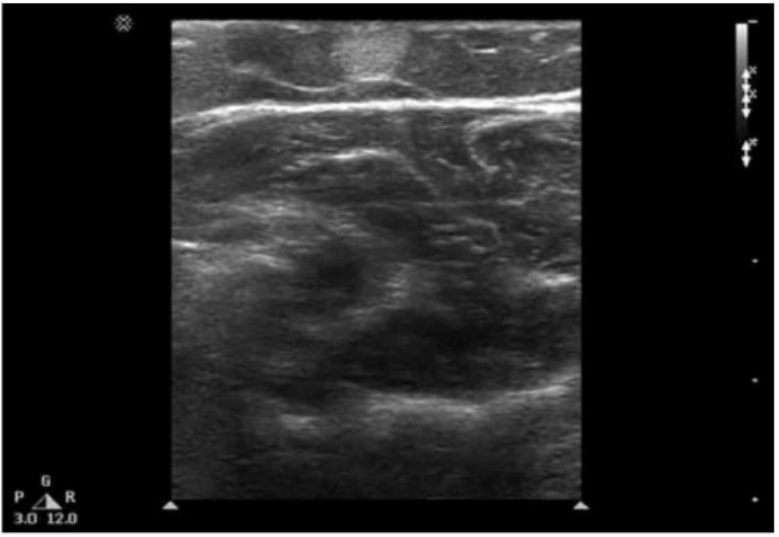

Which condition is most consistent with the sonographic appearance in this image of the abdominal wall?

Answer : A

The ultrasound image demonstrates a well-defined, ovoid, hypoechoic to isoechoic mass within the subcutaneous tissue of the abdominal wall. The lesion appears compressible and shows linear striations parallel to the skin surface --- a classic appearance of a lipoma.

Lipomas are the most common benign soft tissue tumors and frequently arise in the subcutaneous tissue. They are composed of mature adipose tissue and are typically asymptomatic unless large or compressing adjacent structures.

Sonographic features of a lipoma:

Isoechoic to mildly hyperechoic or hypoechoic relative to subcutaneous fat

Oval or elliptical in shape with well-defined margins

Internal linear striations or ''feathered'' echotexture

Compressible and non-vascular on Doppler imaging

Located in subcutaneous fat plane parallel to the skin surface